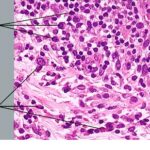

Differential Diagnosis. Great difficulty may be encountered in the differentiation of a nodular melanoma from an atypical dermal or compound nevus. The actual incidence of a wrong diagnosis is not inconsiderable, judging from the frequency with which pathologists disagree in their opinions. When there is doubt, the uncertainty should be acknowledged and the differential diagnosis should be clearly indicated so that appropriate therapeutic intervention can be planned. Incisional biopsies are a common source of interpretive difficulty. The site of melanocytic lesions that have been partially removed by shave or punch biopsy should be excised to assure complete removal if there is any doubt at all about the diagnosis. |

The most important attributes that differentiate the tumorigenic vertical growth phase of melanoma from nevi include asymmetry, lack of maturation of lesional cells with descent into the dermis, mitotic activity, and uniform cytologic atypia. Apoptotic tumor cells, which often accompany mitotically active lesions, may also be of assistance. |

The most important differential diagnostic consideration for nodular melanoma is the Spitz nevus. The criteria for this distinction are presented in Table 28-3 and discussed in the section Spitz Nevus. |